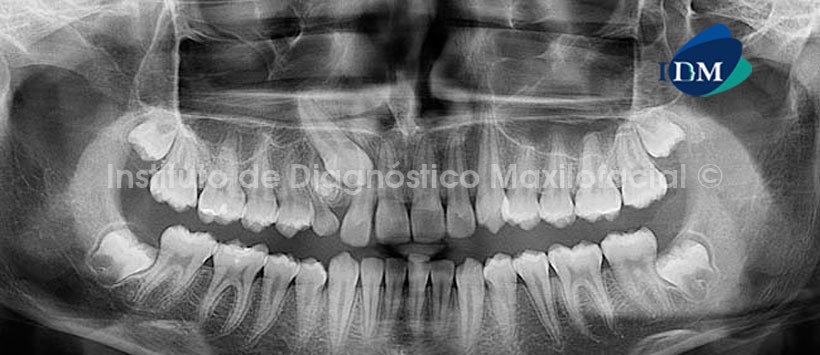

En la radiografía panorámica observamos una imagen radiopaca de densidad dentaria, con halo radiolúcido circundante, corticalizada; sugerente de lesión benigna compatible con Odontoma Compuesto, el cual condiciona la retención y mesialización de la pieza 1.3 produciendo la divergencia radicular de las piezas 1.2 y 5.3, la cual se encuentra en persistencia. (Fig. 1)